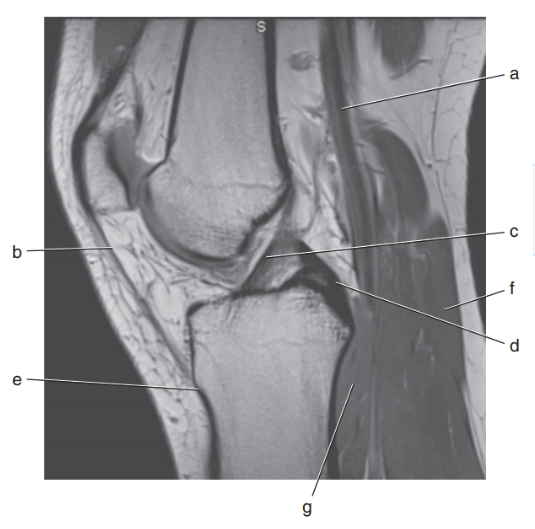

What letter is the intervertebral disc at L2-3 ?

C

What is letter D ?

nucleus pulposis

What is letter E ?

annulus fibrosis